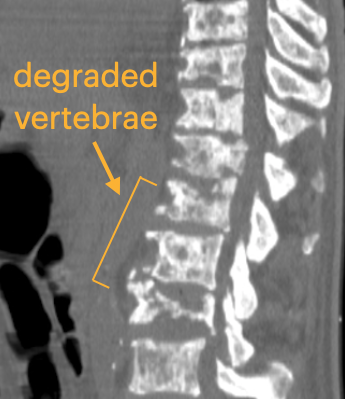

Here is an example of how the degraded vertebrae look in CT scans and the challenges of segmentation in Slicer.

Note the interior holes because of the heterogeneous nature of the lytic bone.